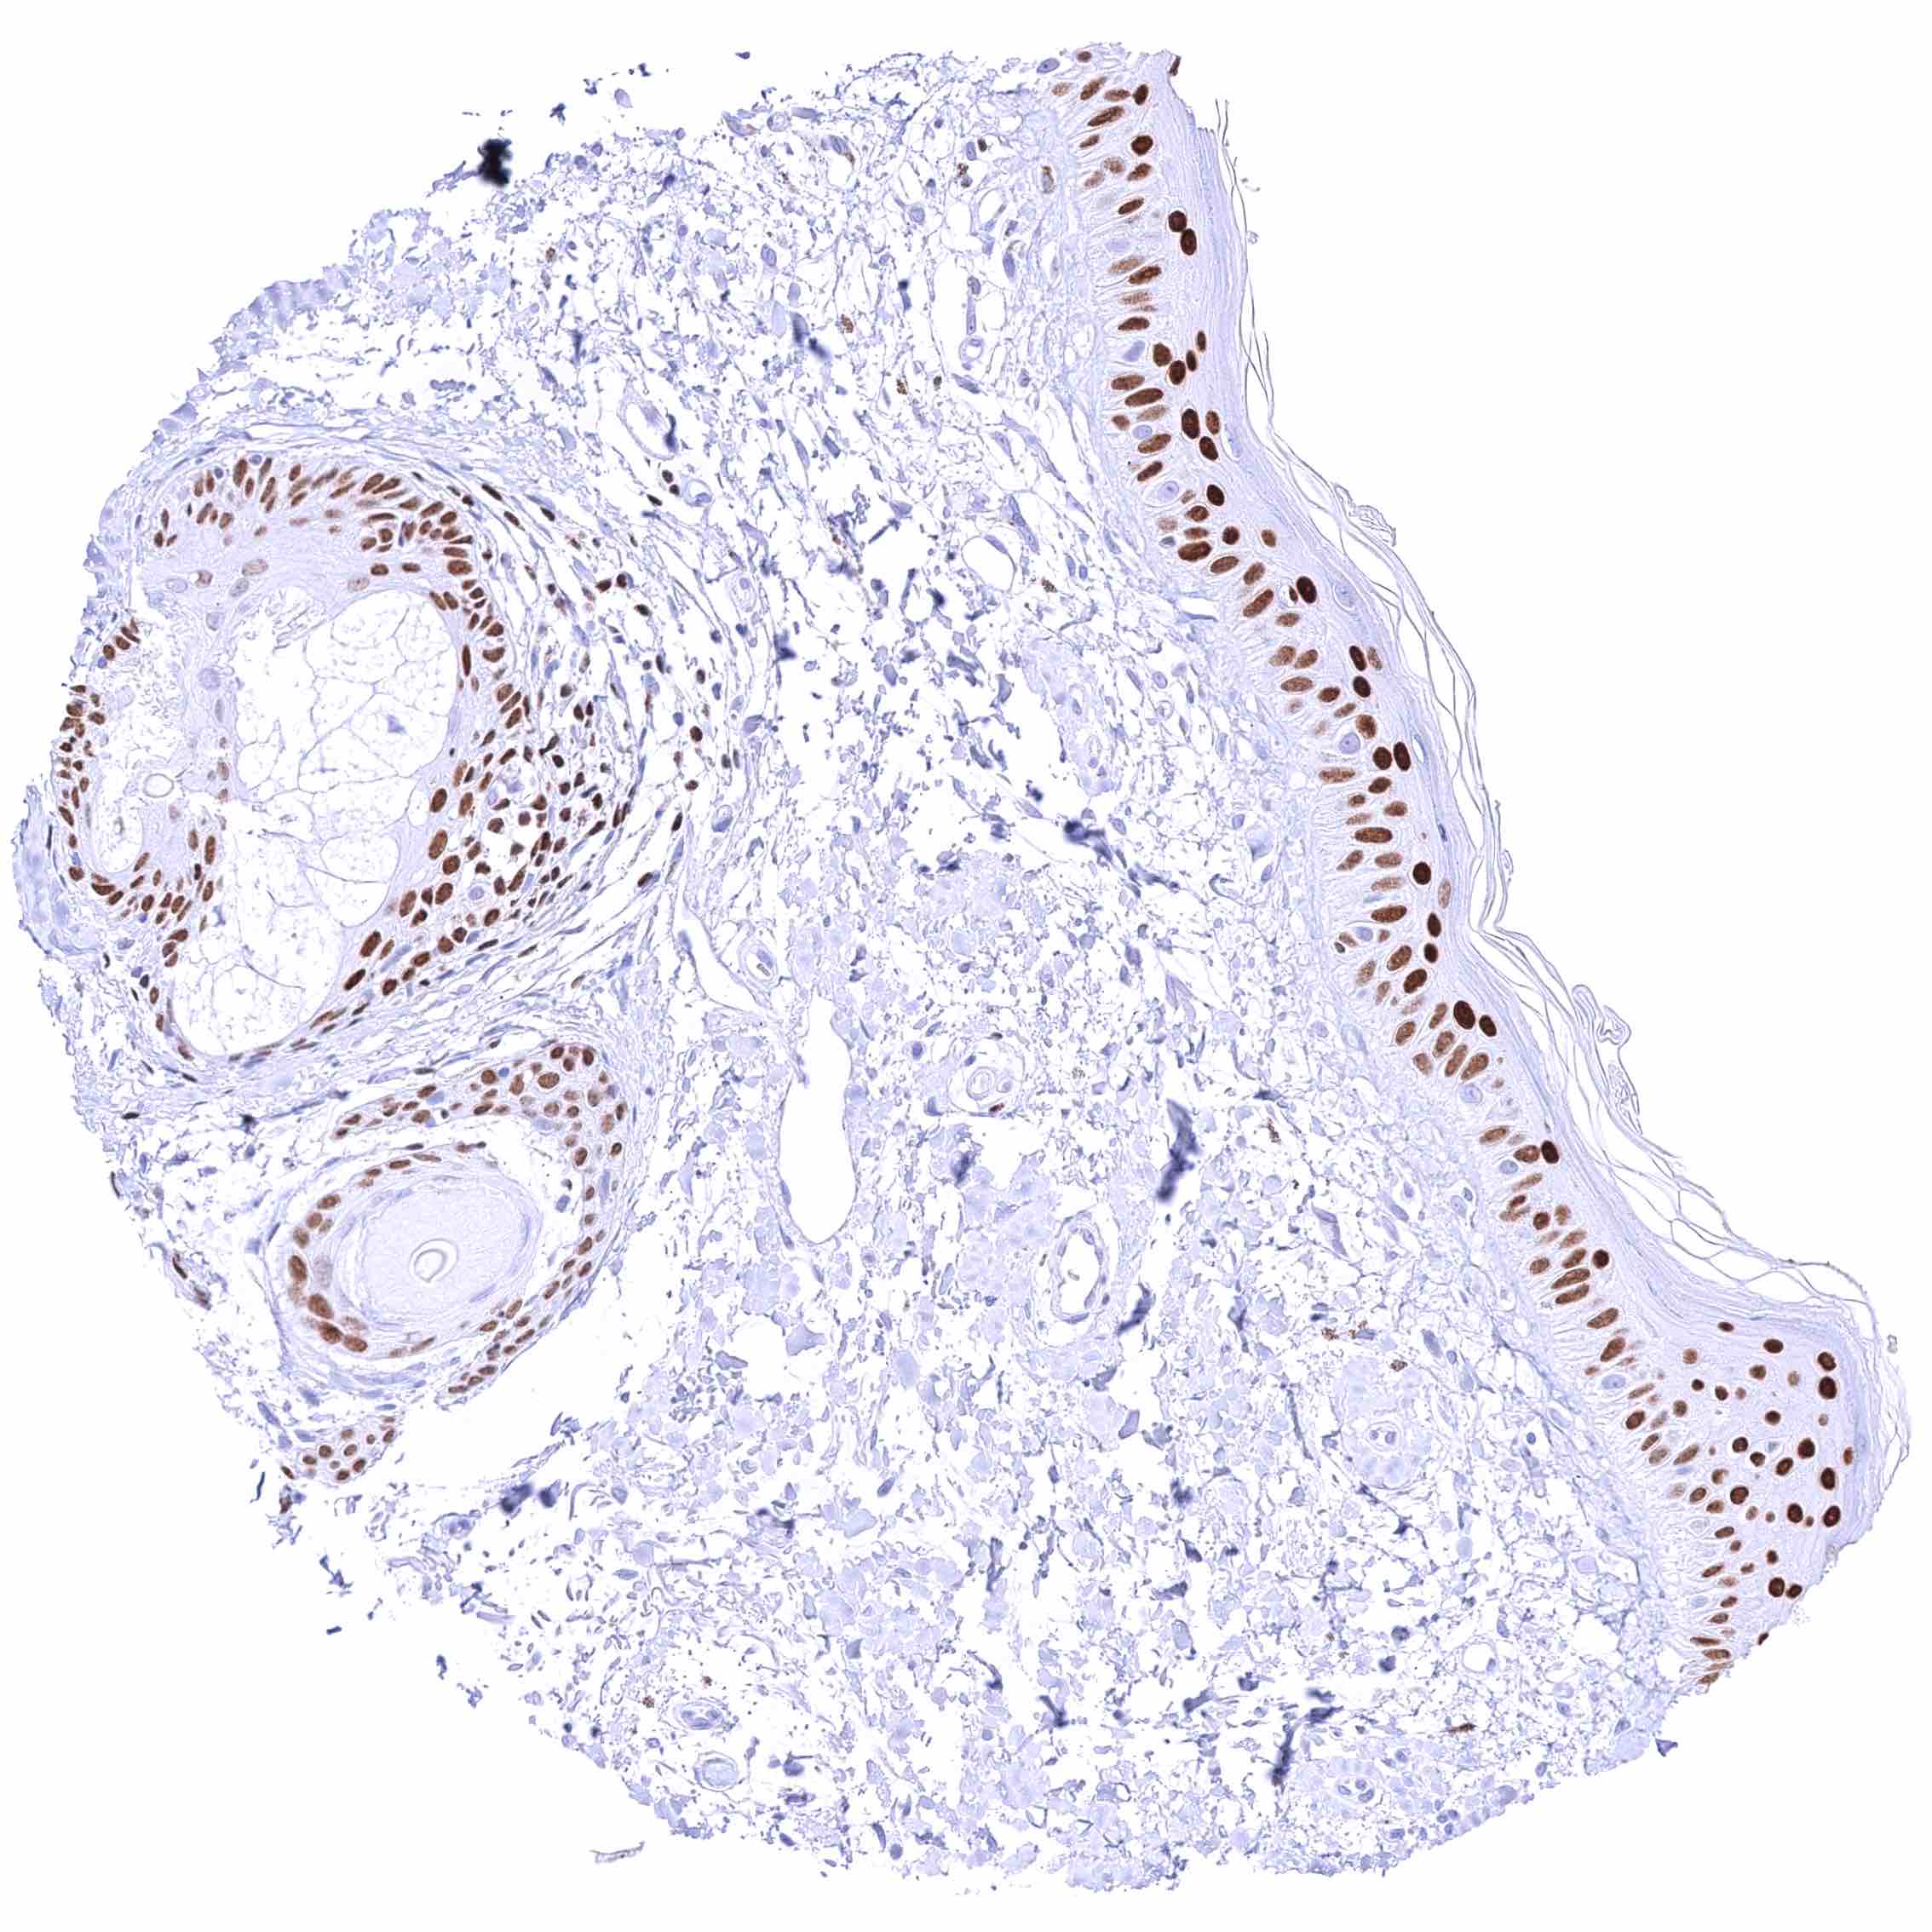

Skin – Strong nuclear GATA3 staining of squamous epithelial cells.

Skin, hair follicel and sebaceous glands – Moderate nuclear GATA3 staining of cells of hair follicles and of peripheral germinative cells of sebaceous glands. GATA3 staining is faint or absent in cells of sebaceous glands.

Skin, hair follicel and sebaceous glands – Strong nuclear GATA3 staining of squamous epithelial cells, cells of hair follicles, and peripheral germinative cells of sebaceous glands. Nuclear GATA3 staining is faint or absent in cells of sebaceous glands.